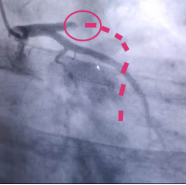

50岁的张先生,吃了一根冰棍后2小时,突发心前区剧烈闷痛,大汗淋漓,烦躁虚弱。到邵逸夫医院下沙院区急诊室就诊,心电图检查提示急性ST段抬高型心肌梗死,1小时内急诊紧急手术开通血管,手术中发现前降支近段起完全闭塞,于是进行前降支血栓抽吸,并植入支架。在手术后,患者胸痛症状就明显缓解。

虚线处本该有血管(图片来源:邵逸夫医院公众号)